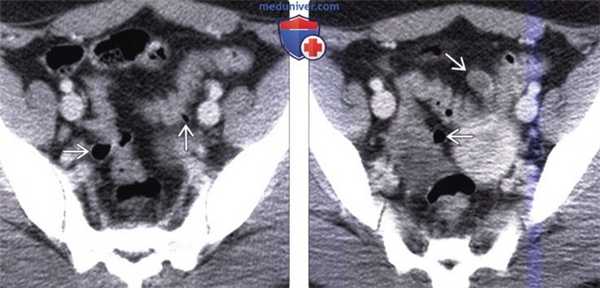

(Слева) На КТ у женщины 21 года, страдающей ожирением и сахарным диабетом, предъявляющей жалобы на чередование за -поров и диареи, визуализируются множественные дивертикулы, проецирующиеся вне поверхности сигмовидной ободочной кишки.

(Справа) На другом КТ срезе у этой же пациентки визуализируется еще один дивертикул. В настоящее время, наряду с эпидемией ожирения, дивертикулез обнаруживается даже у молодых людей, как в этом случае. И дивертикулез, и ожирение напрямую связаны с употреблением в пищу продуктов, богатых жиром и бедных растительными волокнами, а также с гиподинамией.